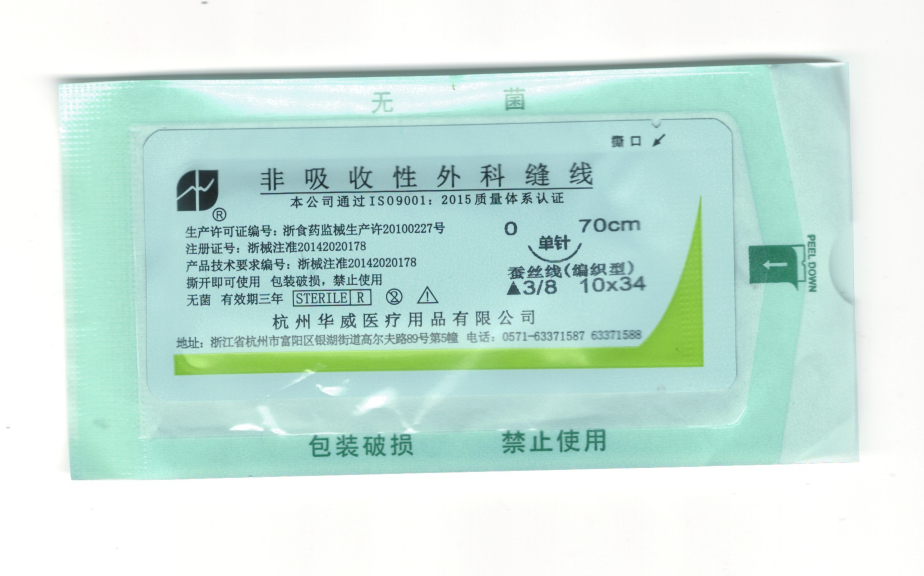

非吸收性外科縫線2